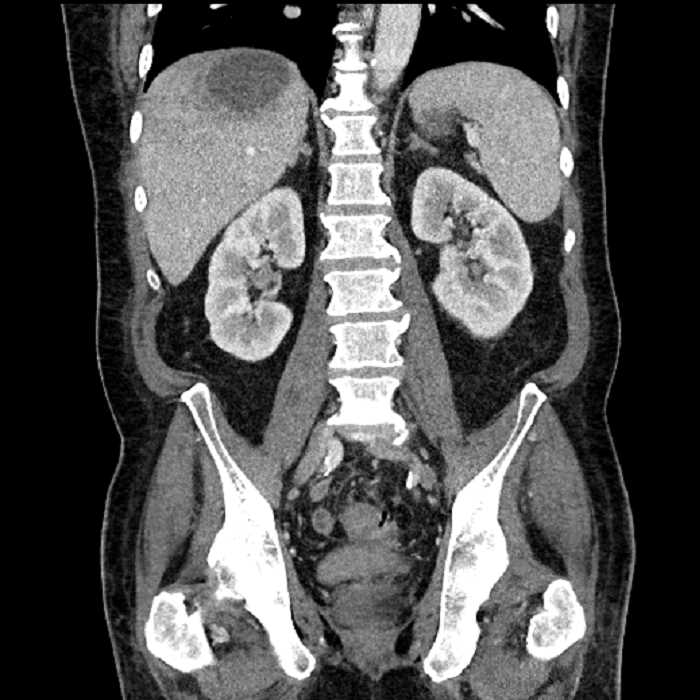

• Large fluid density structure in hepatic segments 7 and 8 measuring 10 x 7 x 7 cm with internal septation and circumferential ill-defined low density compatible with edema

• Peripherally enhancing subcapsular collections along the anterior margin of the left hepatic lobe measuring 3 x 1 cm and 2 x 1 cm

• Clearly marginated fluid density structure in segment 7 and several other scattered tiny hypodensities, which likely represent cysts

• High grade stenosis of the left common iliac artery, with the left internal and external iliac arteries remaining patent

• Hepatic abscess

Acute sigmoid diverticulitis complicated by a small contained perforation and a large abscess in the right hepatic lobe. Additional small subcapsular abscesses along the anterior margin of the left hepatic lobe.

High grade stenosis of the left common iliac artery. The left external and internal iliac arteries are patent.

Hepatic abscess showing the double target sign with low density internally surrounded by a thin inner enhancing rim (red arrow) and ill-defined outer low density rim (yellow arrow). Blue arrow indicates an internal septation. Red arrows: additional smaller subcapsular abscesses. Red arrow: focal contained perforation associated with diverticulitis.